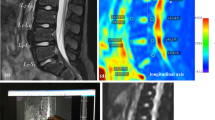

After the incubation chamber had been refilled, T1-weighted dynamic scans were repeated (approximately one every three minutes) for a period of several hours—average period 17 h, longer or shorter according to scanner availability. The parameters of each scan were: TE 3.9 ms, TR 20 ms, flip angle 30°, 30 slices, slice thickness 2 mm, slice overlap 1 mm, FOV 60 × 60 mm, 64 × 64 pixels, resampled to 576 × 576 pixels so as to match the anatomical scan. Example images, showing the time variation of greyscale values in the disc, are given in Fig. 2 (lower panels). The anatomical scan and the dynamic scans were pre-processed using the “CLEAR” function in the Philips imaging software, which corrects the image uniformity on the basis of a coil sensitivity map acquired in a reference scan.

(top left) Central slice from an anatomical scan; (top right) schematic diagram of the 13 disc ROIs; N = nucleus, IA = inner annulus and OA = outer annulus; individual regions are labelled as inner left annulus = ILA, outer posterior annulus = OPA, etc. (the positions of the various regions have not been adjusted to match the anatomical scan); (bottom) central slices at 4-hour intervals from a series of dynamic scans for the diffusion of Gadovist, showing the disc in the centre of the incubation chamber and the oil reference outside; (the bright areas near the chamber walls show regions of incubation medium, where the image slice falls outside the dialysis membranes)

The initial high-resolution anatomical scan of the disc (Fig. 2) allows the annulus, with its distinctive rings, to be distinguished from the nucleus. On the basis of this scan, 13 ROIs were positioned on the central axial slice of each dynamic scan, as shown in Fig. 2; each ROI has approximate volume 2 mm3 (1 mm2 in plane); positions were varied to correspond with the different dimensions of individual discs. For each ROI within each sample, data were obtained on the variation of greyscale values with time, reflecting the diffusion of the active component of the contrast agent into the disc. Examples are given in Fig. 3.